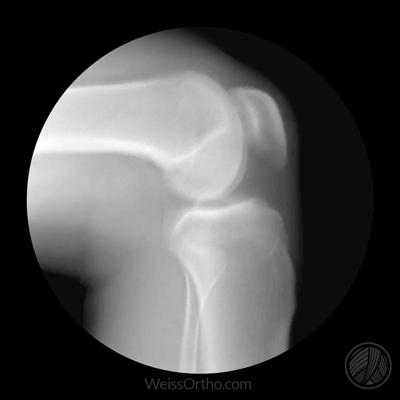

如果存在着症状,那么如何才能确诊是否存在着半月板损伤呢?很多朋友可能会想拍一个膝关节的x线片子吧,但是对不起,因为半月板是软骨,在x线上是不显影的,对于膝关节半月板损伤的确诊还是要依靠核磁检查,通过核磁检查不仅可以明确半月板是否存在损伤,还可以给予半月板进行损伤的分级,另外可以判断关节腔内是否有积液,是否有其他结构的问题。

下面就是不同程度的半月板损伤的模拟图像以及核磁影像,谢医生给大家详细的说一说:

半月板损伤在核磁影像上主要分三度,不同的损伤程度决定了不同的治疗办法。